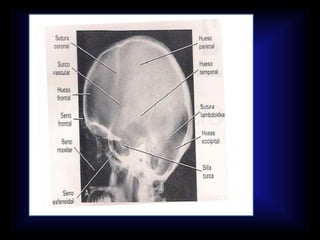

CEFALOMETRIA • A travésde los estudios cefalométricos, el ortodoncista logrará un conocimiento más profundo de las estructuras involucradas, medirlas, describirlas y estudiar sus interrelaciones. • La cefalometría no es una ciencia exacta, por las dificultades de localización de los puntos y la inexactitud de los exploradores a la hora de encontrarlos; no obstante es, junto a los modelos dentales, una de las principales herramientas diagnóstica en ortodoncia. • La cefalometría se realiza sobre un trazado obtenido del calco de líneas fundamentales de una radiografía lateral de cráneo, obtenida del paciente, según unas normas determinadas que nos permiten estandarizar los resultados y compararlos con patrones normales.

LINEA S-N Representa labase anterior del craneo. S: Silla Turca. N: Sutura Frontonasal.

PLANO BOLTON PLANO BA-N Condilos del occipital N: Nasion Bo: Bolton Ba: Basion

PLANO FRANKFORT HORIZONTAL P: PORION MEATO AUDITIVOEXT O: ORBITAL PUNTO INFERIOR DE LA ORBITA

PLANO PALATINO ENP ENA Espina nasalposterior Espina nasal anterior